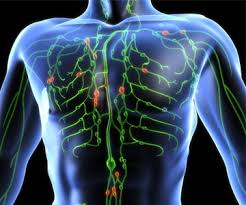

Lymphoma is cancer that starts in the lymph glands or other organs of the lymphatic system. Those affected may feel tired or be itchy. Lymphoma staging is identifying where the disease is located and the potential areas of your body it may have spread to. We have more information about signs and symptoms of lymphoma. Hodgkin lymphoma (hodgkin disease or hl) is the less common form of lymphoma, affecting about 9,000 adults and children in the united states each year.

Signs and symptoms may include enlarged lymph nodes, fever, drenching sweats, unintended weight loss, itching, and constantly feeling tired. Get information about the main types here. Not all such lumps are a sign of lymphoma. We have more information about signs and symptoms of lymphoma. Hodgkin lymphoma (hl), of which there are six types, accounts for around 10% of all lymphoma cases in the united states. Lymphocytes travel through the blood and lymphatic system to defend the body against foreign invaders like bacteria and viruses. It is part of the immune system. Lymphoma is a general term for cancers that start in the lymph system (the tissues and organs that produce, store, and carry white blood cells that fight infections).

Lymphoma can affect all those areas as well as other organs throughout the body. Lymphoma is a cancer of the lymph (or lymphatic) system. Hodgkin lymphoma (hl) is a type of lymphoma in which cancer originates from a specific type of white blood cells called lymphocytes. Hodgkin lymphoma (hodgkin disease or hl) is the less common form of lymphoma, affecting about 9,000 adults and children in the united states each year. There are two major types of hodgkin lymphoma: Specifically, lymphoma is a cancer that affects lymphocytes, which are a type of white blood cell. Hodgkin lymphoma can develop anywhere in the body where lymphocytes are found. The lymph system is a network of tissue, vessels, and fluid (lymph). The lumps themselves are swollen lymph nodes, and they typically appear in the neck, armpit, or groin. It is normal for lymph nodes to swell as they fill with white blood cells as part … continued Learn about lymphoma, a cancer that starts in the lymph system. Which lymphoma treatments are right for you depends on the type and stage of your disease, your overall health, and your preferences. The name often refers to just the cancerous versions rather than all such tumours.

Leukemia and lymphoma are both forms of blood cancer, but they affect the body in different ways. Lymphocytes travel through the blood and lymphatic system to defend the body against foreign invaders like bacteria and viruses. It is normal for lymph nodes to swell as they fill with white blood cells as part … continued Get information about the main types here. Lymphoma is a general term for cancers that start in the lymph system (the tissues and organs that produce, store, and carry white blood cells that fight infections). Explore the links on this page to learn more about lymphoma. The lumps themselves are swollen lymph nodes, and they typically appear in the neck, armpit, or groin. Lymphoma is a group of blood malignancies that develop from lymphocytes (a type of white blood cell).

Diagnostic testing is used to detect the cancer's stage, which helps the doctor determine an appropriate course of treatment. Lymphoma a group of blood cancers that develop in the lymphatic system. Lymphoma staging is identifying where the disease is located and the potential areas of your body it may have spread to. These cancers change the way blood cells behave and how well they work. Leukemia and lymphoma are both forms of blood cancer, but they affect the body in different ways. Many types of lymphoma exist. But it is very rare, accounting for about 2 percent of all lymphoma diagnoses. There are two main types of lymphoma, which spread and are treated differently: Which lymphoma treatments are right for you depends on the type and stage of your disease, your overall health, and your preferences. The two main kinds of lymphoma are— hodgkin lymphoma, which spreads in an orderly manner from one group of lymph nodes to another. The lymphatic system includes the lymph nodes (lymph glands), spleen, thymus gland and bone marrow. These cells are in the lymph nodes, spleen, thymus, bone marrow, and other parts of the body. Lymphoma is a cancer of the lymph (or lymphatic) system.

Lymphoma is a group of blood malignancies that develop from lymphocytes (a type of white blood cell). Hodgkin lymphoma can often be cured. It is normal for lymph nodes to swell as they fill with white blood cells as part … continued Specifically, lymphoma is a cancer that affects lymphocytes, which are a type of white blood cell. Lymphomas refers to types of cancer that begin in the lymphatic system (the various lymph glands around the body) when abnormal white blood cells grow. The lymphatic system includes the lymph nodes (lymph glands), spleen, thymus gland and bone marrow. The main difference is that leukemia affects the blood and bone marrow, while lymphomas mainly. Lymphoma can affect all those areas as well as other organs throughout the body.

Hodgkin lymphoma can develop anywhere in the body where lymphocytes are found. Those affected may feel tired or be itchy. Diagnostic testing is used to detect the cancer's stage, which helps the doctor determine an appropriate course of treatment. Lymphoma is the most common type of blood cancer. Lymphomas refers to types of cancer that begin in the lymphatic system (the various lymph glands around the body) when abnormal white blood cells grow. Lymphoma is a group of blood malignancies that develop from lymphocytes (a type of white blood cell). This is usually in the neck, armpit or groin. But it most often begins in lymph nodes in the chest, neck or under the arms. It develops in lymphocytes, which are a type of white blood cell. Lymphoma is a general term for cancers that start in the lymph system (the tissues and organs that produce, store, and carry white blood cells that fight infections). These cells are in the lymph nodes, spleen, thymus, bone marrow, and other parts of the body. When you're looking for information about lymphoma, make sure you know which type you want to know about. Symptoms from lymphoma in the chest when lymphoma starts in the thymus or lymph nodes in the chest, it may press on the nearby trachea (windpipe), which can cause coughing, trouble breathing, or a feeling of chest pain or pressure.